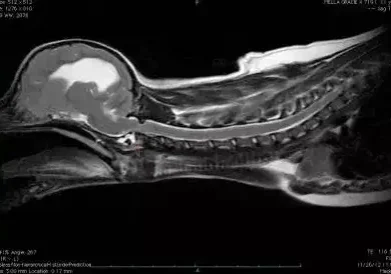

Gracie was evaluated weekly until she was about six months of age. She was then admitted for surgical fusion of her neck. Below is her magnetic resonance imagining (MRI) used for surgical planning and to evaluate for spinal cord damage.

Gracie Pre Op Mri

Gracie’s pre-operative MRI.

Note that there is still subluxation at C1-C2.